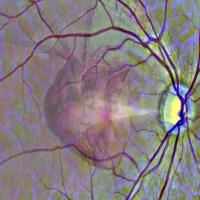

AI-based systems can help identify rapidly advancing age-related macular degeneration

Researchers supported by the NEI are developing artificial intelligence/machine learning (AI/ML)-based systems that not only screen for AMD but also predict which patients will likely progress to late within two years.

Image of retina